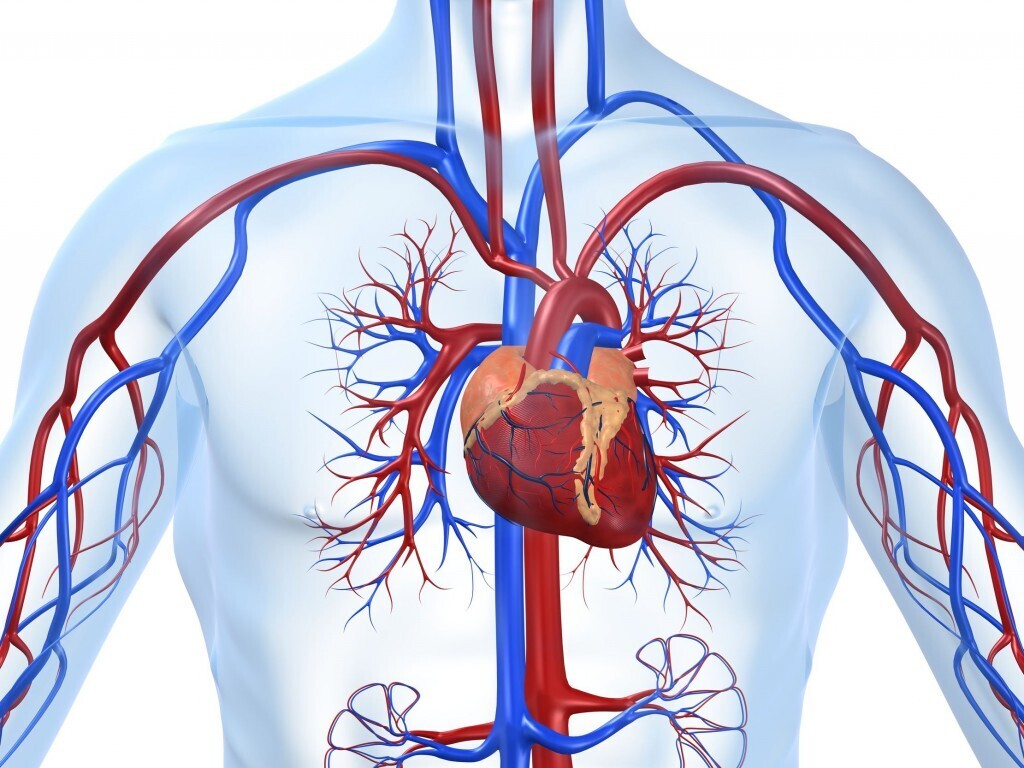

Какие продукты необходимы сердцу прежде всего?

Рацион питания, нужный сердцу, включает фрукты и овощи, крупы и бобовые, орехи, нежирное мясо, морепродукты растительные масла.

Особенно полезны:

1. Морская рыба, в которой высокая концентрация полиненасыщенных жирных кислот, селена и цинка.

1. Грецкие орехи, содержащие полезные растительные жиры и белки.

1. Оливковое масло, в составе которого антиоксиданты, способствующие понижению уровня холестерина.

1. Авокадо, еще один источник нужных сердечной мышце жирных кислот и минералов.

1. Апельсины и другие цитрусовые, поскольку в них содержится аскорбиновая кислота и пектин.

1. Овсянка, поддерживающая стабильный метаболизм и способствующая выведению токсинов.

1. Вишня и черника богаты антоцианами, очищающими стенки сосудов.

Включать в свой рацион нужно нежирные кисломолочные продукты, вареные яйца, но не более двух штук в неделю, отварную индейку и телятину.

Правильное питание позволит надолго сохранить высокую работоспособность сердца и хорошую проходимость сосудов. =============================================================================================================================================== поставьте пожалуйста ЛАЙК == оставьте комментарий === заранее благодарю ================================================================================================================================================